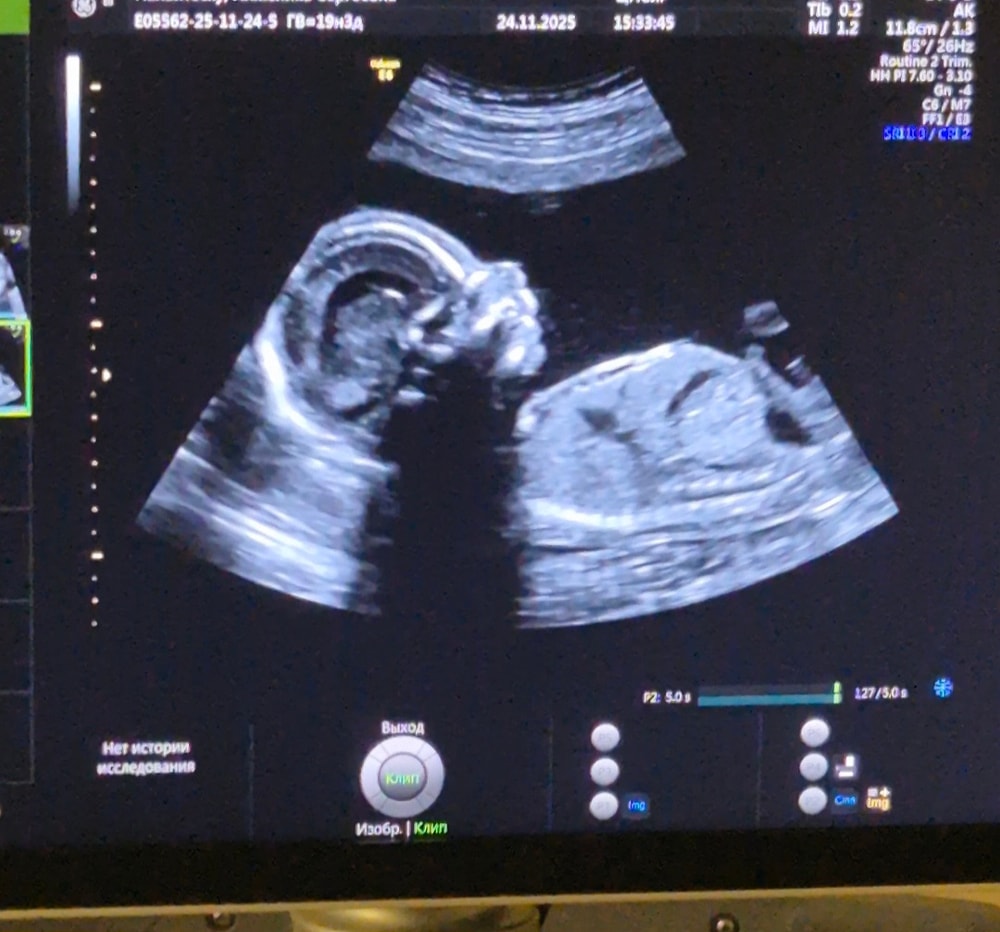

Добрый вечер девочки))

пришла с 2 скрининга

По М срок 19,2 дня

по 1 скрининг срок 20 недель ровно сегодня

по УЗИ 20,5 неделя 🙄почему разные ???

по росту живота и кости ног и рук вообще 22 недели

вес 502 👀это крупный или мало?

у нас мальчик ))

у кого так было,сколько родили к сроку ))??